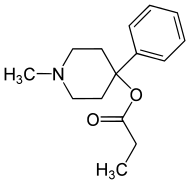

Phenylpiperidines

- Pethidine (meperidine)

- Ketobemidone

- MPPP

- Allylprodine

- Prodine

- PEPAP

- Promedol